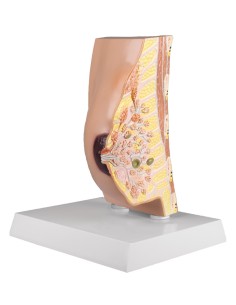

Modèle de palpation mammaire, trois seins simples sur support - 3B Scientific L55

Modèle de palpation mammaire, trois seins simples sur support - 3B Scientific L55

Modèle de palpation mammaire, à suspendre - 3B Scientific L51

Modèle de palpation mammaire, à suspendre - 3B Scientific L50